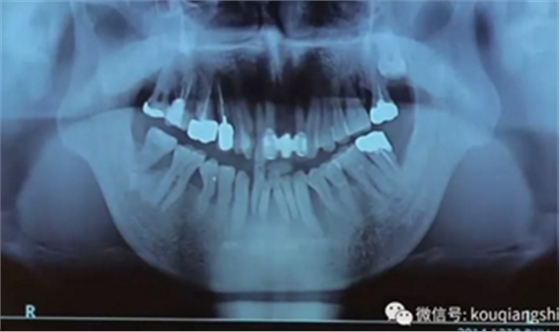

这位患者是2014年来到我们医院

从CT上我们可以看到#14,15,17的牙槽骨被牙齿长期的牙周炎破坏的非常严重,但是因为当时患者不想拔牙,所以暂时保留下来。

但是1年之后,因为患者实在无法继续使用这些牙齿

所以到我们医院进行了拔牙

9周后,我们发现黏膜组织愈合的非常好

11周翻开黏膜,我们发现形成的骨已经完全满足我们种植的需要

我们正常进行种植,并在缝隙处放置骨粉。